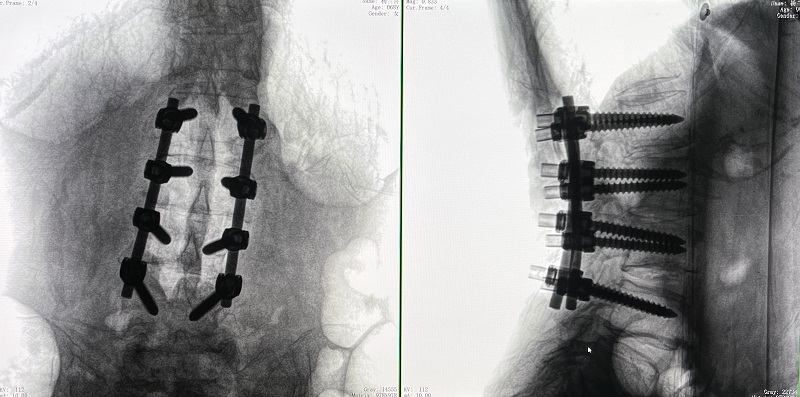

術后圖像